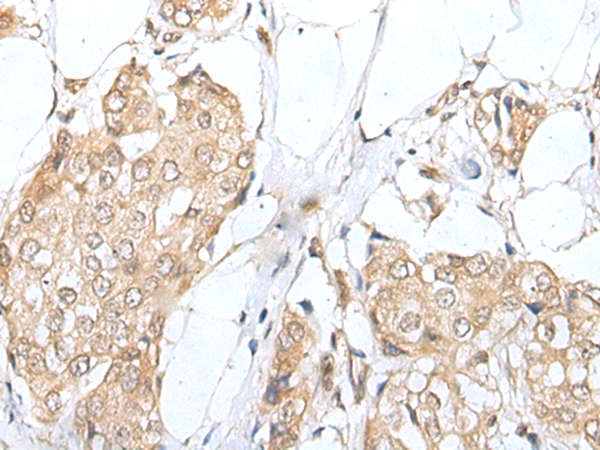

IHC (Immunohiostchemistry)

(The image on the left is immunohistochemistry of paraffin-embedded Human breast cancer tissue using ZNF263 Antibody at dilution 1/40, on the right is treated with fusion protein. (Original magnification: x200))